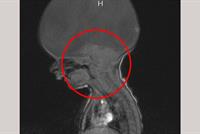

احتفل الطفل آرون الذي ولد بدون دماغ ، باستثناء قسم صغير في نهاية عنقه ، وهو الجزء الذي يسمح له بالتنفس والحركة فقط ،بعامه الثاني ، الأمر الذي شكل صدمة لوالدته التي علمت بالأمر بعد ولادتها بدقيقتين فيما أخبرها الأطباء أنه قد يموت في أي لحظة.